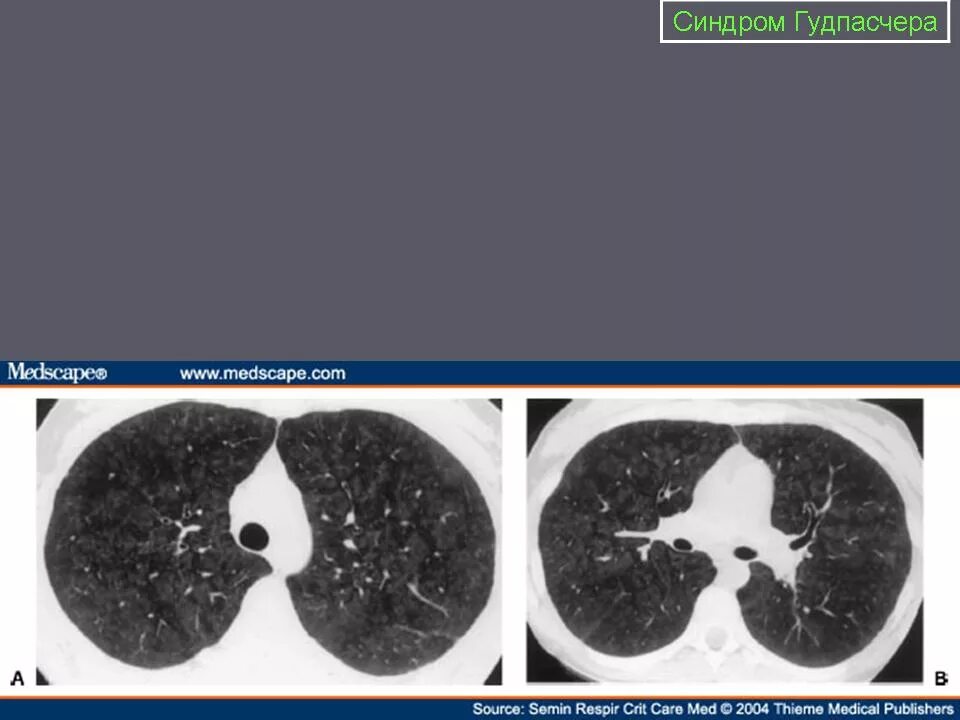

Синдром гудпасчера это